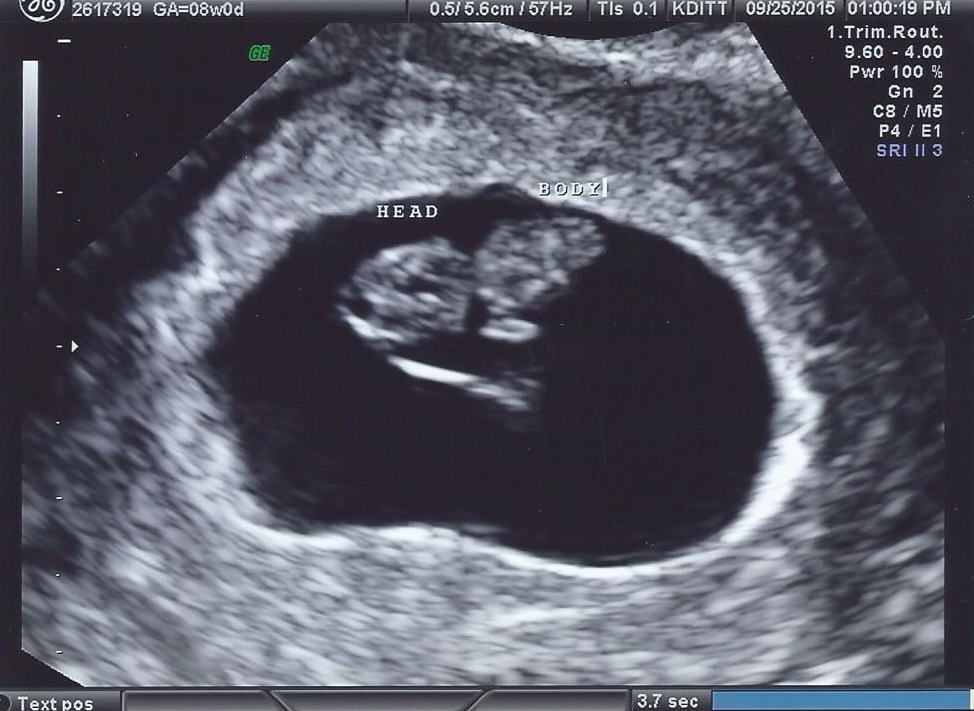

A little blurrier than others, but I am at 8w by lmp and Speck measured as 8w4d and heartbeat at 150! Such a relief given past experiences! We aren't out of the woods until 1st trimester ends of course, but so thrilled there is a baby in there, and all is well at this point!